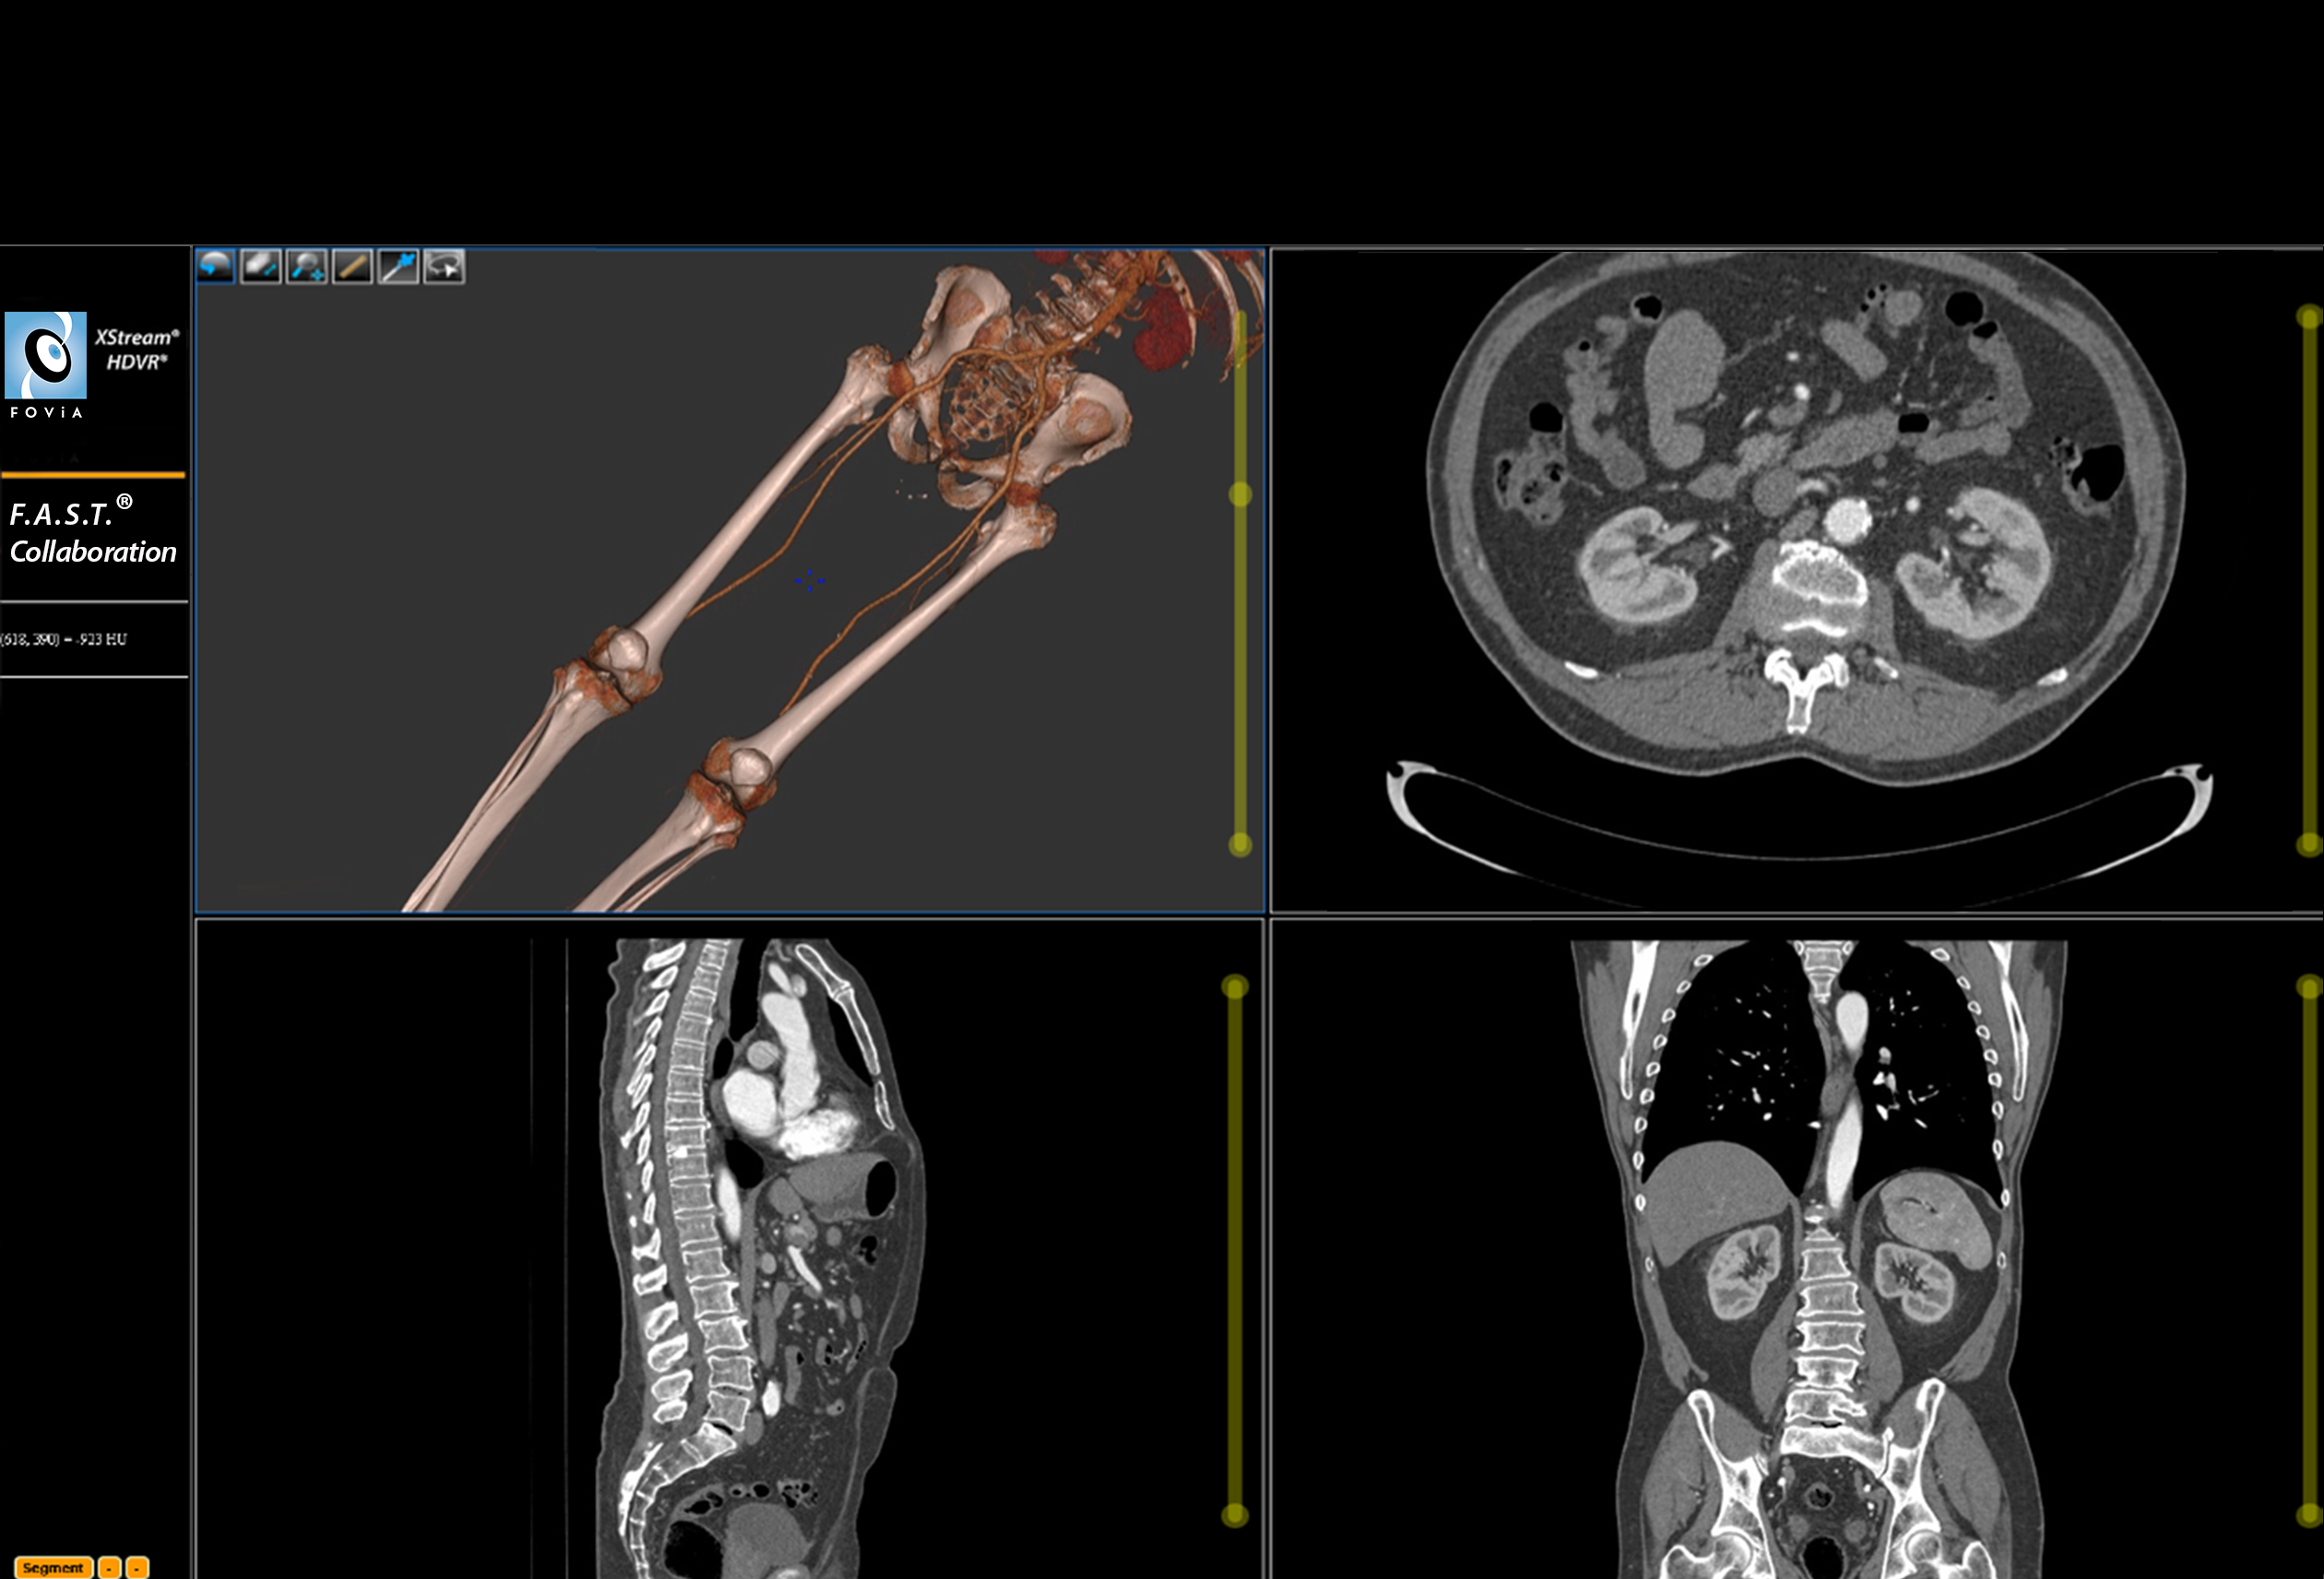

F.A.S.T. Collaboration Workflow

F.A.S.T. Collaboration Workflow